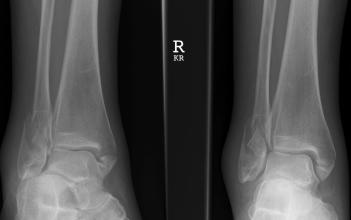

1.X線檢查

凡疑為骨折者應(yīng)常規(guī)進(jìn)行X線拍片檢查,可顯示臨床上難以發(fā)現(xiàn)的不完全性骨折、深部的骨折、關(guān)節(jié)內(nèi)骨折和小的撕脫性骨折等,即使臨床上已表現(xiàn)為明顯骨折者,X線拍片檢查也是必需的,可以了解骨折的類型和具體情況,對(duì)治療具有指導(dǎo)意義。

X線攝片應(yīng)包括正、側(cè)位片,必須包括鄰近關(guān)節(jié),有時(shí)需加攝斜位、切線位或健側(cè)相應(yīng)部位的X線片。